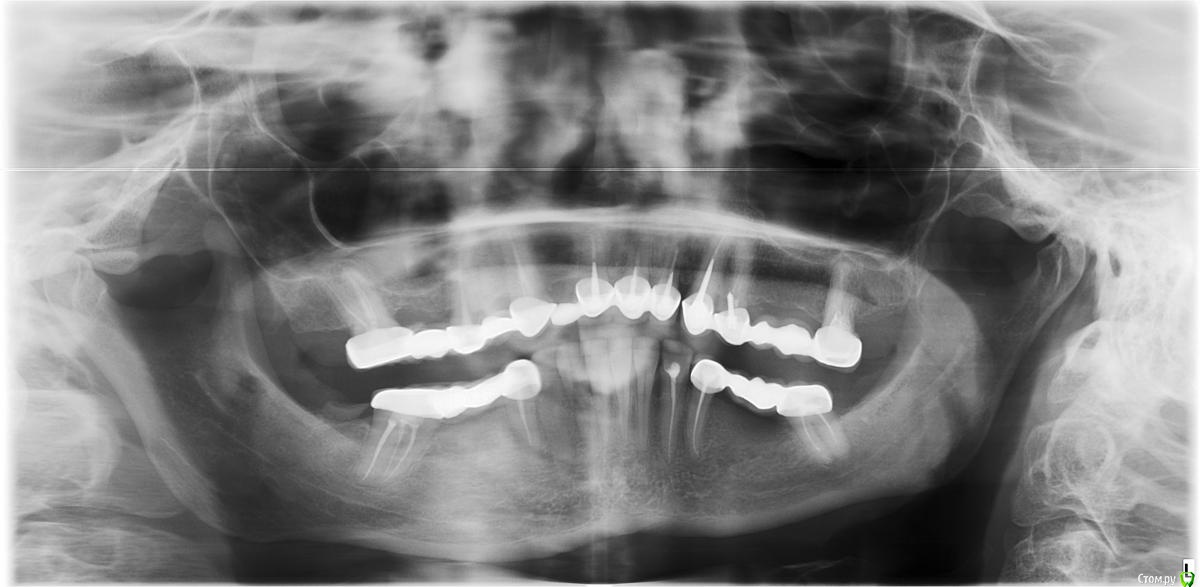

Arsinoya Опубликовано 5 октября, 2019 Поделиться Опубликовано 5 октября, 2019 Полтора года назад протезировала зубы, все было хорошо за исключением левого верхнего моста, он мне эстетически не понравился и решили его переделать. Мне сбили этот мост и в процессе сбивания я почувствовала сильную боль в шестом верхнем зубе. Далее уже дома зуб продолжал болеть при надавливании. Врачу я об этом сказала, но он осмотрев снимки успокоил что это пройдет и все впорядке, что болит соседний зуб мудрости, который короткий не закрывали. Поставили новый мост... Через три месяца начался ад... Адские боли в зубе отдающие в висок, за глаз в голову!!! Я опять к врачу, он сказал это зуб мудрости болит и удалил его... Боли не прекратились, я настояла на вскрытии зуба через коробку, врач там увидел перфорацию зубного дна, поставил временную пломбу, через месяц пришла, боли не прекратились, врач поменял временную пломбу на другую, при про чистке каналов боли не было, при надавливании не болит, но остальные сильнейшие боли остались. Болит так, как будто на нерв попало сладкое. Я сделала КТ челюсти, врач осмотрел его и сказал что причин для таких болей не видит, все хорошо! Сейчас постоянные боли, которые стали еще и в верхнюю четверку отдавать. И каждый день обезболивающие плюс аэртал. Посоветуйте пожалуйста что мне делать? Ссылка на комментарий

Мартовский Опубликовано 7 октября, 2019 Поделиться Опубликовано 7 октября, 2019 Шестых зубов у вас нет, ни с лева ни с права, ни с верху ни с низу. Перфорация есть в левой четверке. Что делать, вам уже сказали: обратиться к другому врачу, по интернету такое не вылечить. Ссылка на комментарий